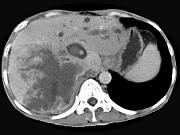

问题 男,44岁,右上腹痛半年,腹部未触及包块,轻度黄疸,AFP阴性,CT检查如图,最可能的诊断为()

选项 A.原发性肝癌 B.胆管细胞癌 C.肝囊肿 D.肝脓肿 E.肝血管瘤

答案 B